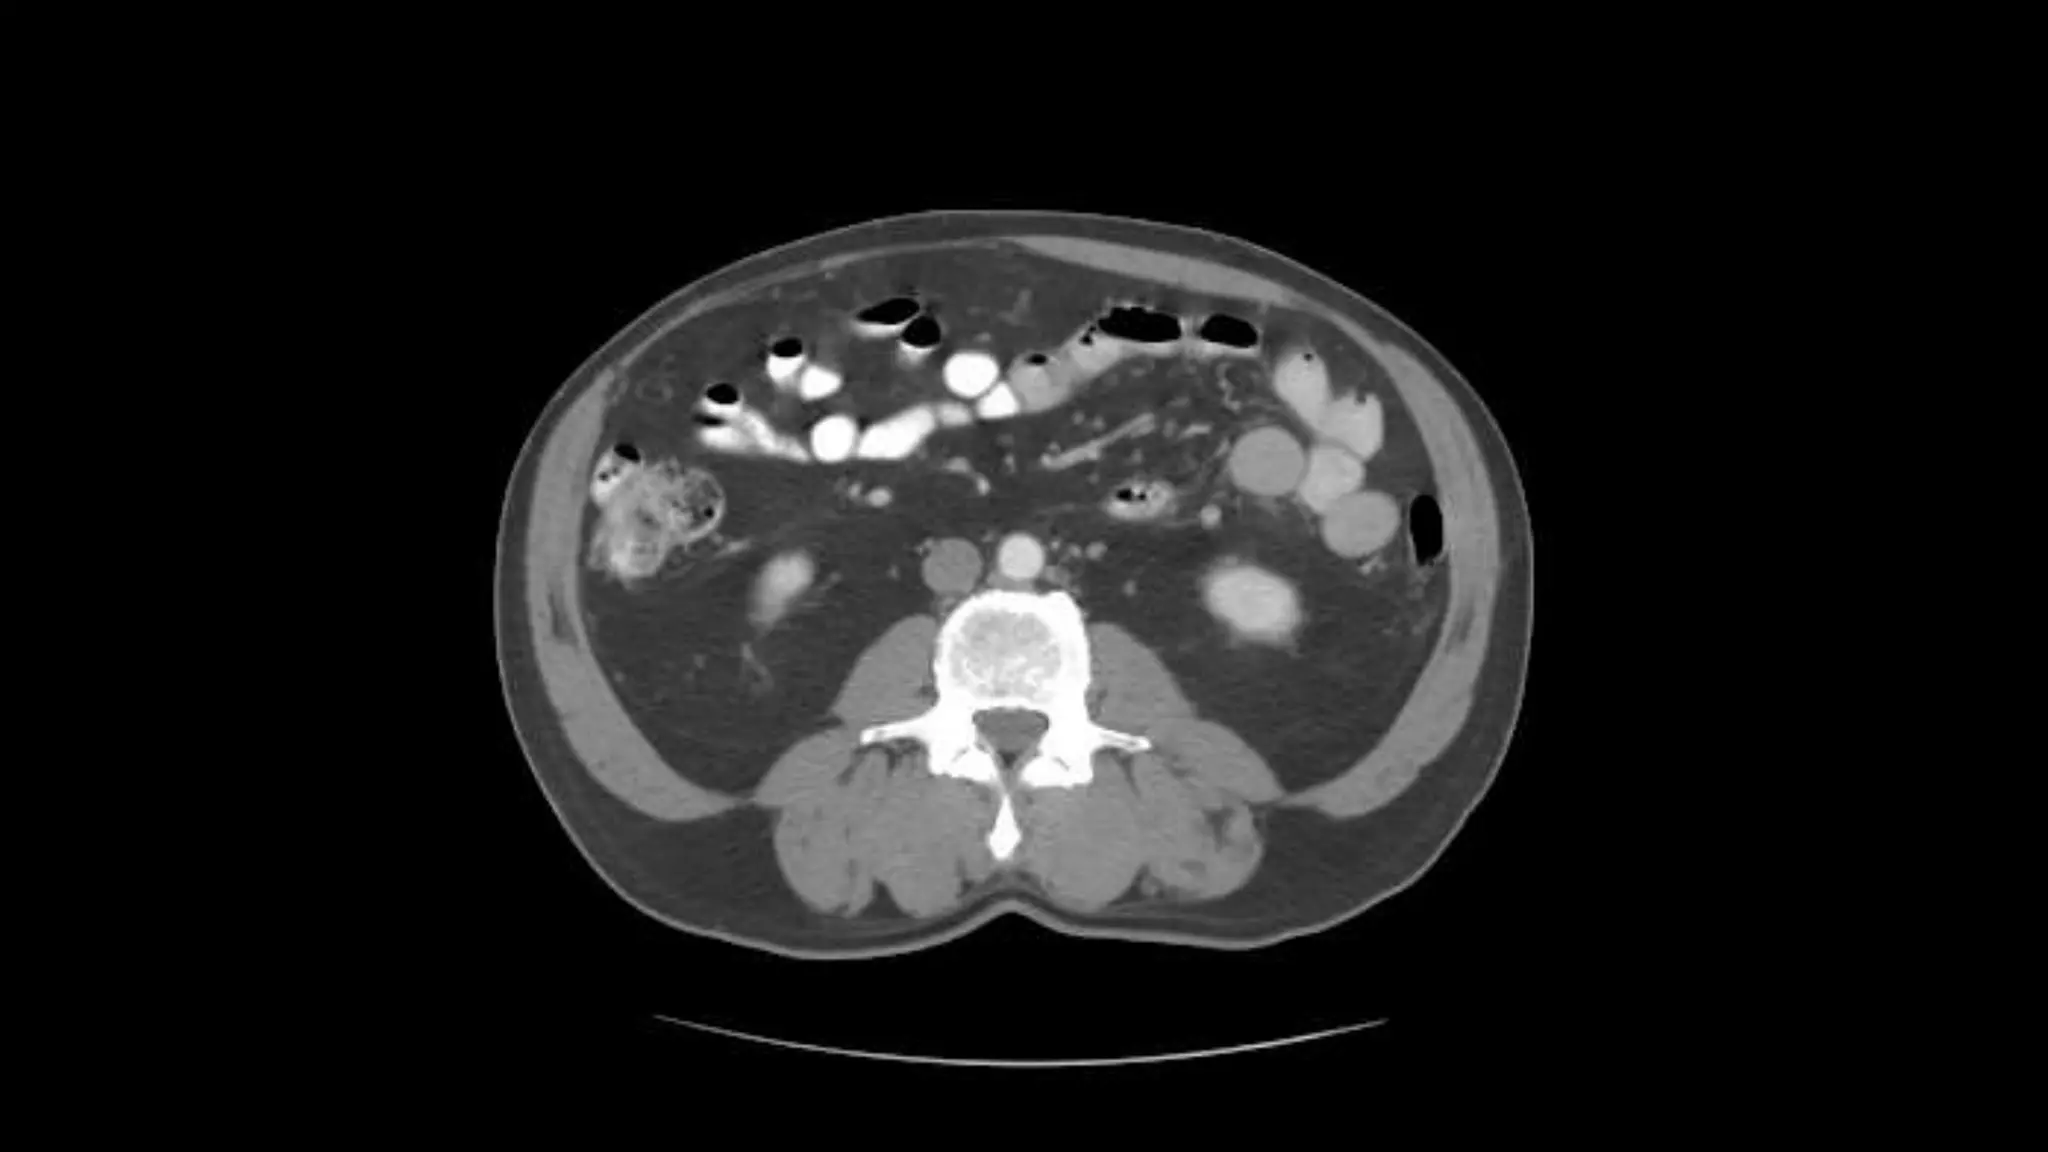

Renal Veins emptyinginto the IVC. We also see the right renal artery branching off the Aorta, follow it down till you see it enter the right kidney. The Superior Mesenteric Vein is outlined on the top of this image. If you follow the SMV up, you will see it empty into the Portal Vein.

Here we seethe right and left renal vein entering into the Inferior Vena Cava. We Also see the left renal artery branching off the aorta and heading toward the left kidney. Page up and down to trace these vessels.

Superior Mesenteric Vein– follow it up as it joins the Splenic Vein to form the Portal Vein